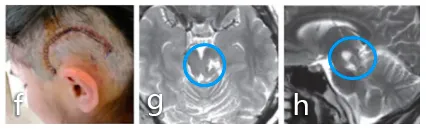

8岁的Emma(左),脑干胶质瘤。化疗无效,头晕、呕吐,生命一点点被吞噬。

巴教授的出现,为这个孩子带来了生的曙光。手术台上,他以精湛的技艺和坚定的信念,与病魔展开了一场惊心动魄的较量。

8年过去,Emma骑着自行车,笑容比阳光灿烂,快乐成长。